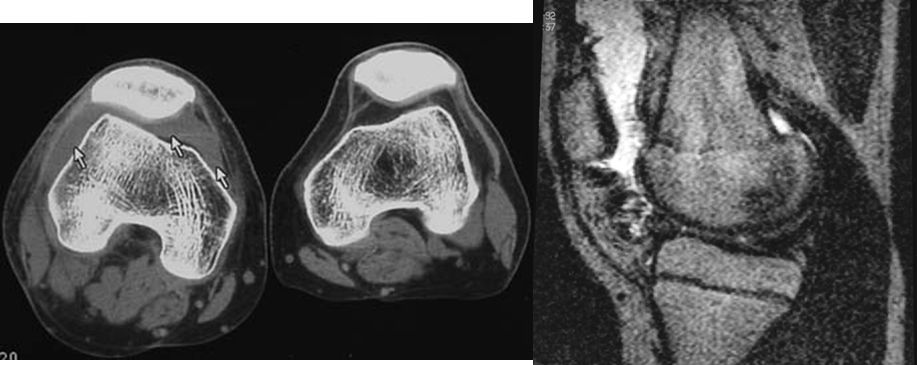

2、X线片(站立或负重位)示关节间隙变窄、软骨下骨硬化、和(或)囊性变、关节缘骨赘形成。

1、关节间隙变窄:成人膝关节间隙为4mm,小于3mm即为关节间隙狭窄,60岁以上的老人膝关节间隙为3mm,小于2mm为关节间隙狭窄。

2、软骨下骨板硬化:软骨下骨板致密、硬化,负重软骨下骨质内可见囊性改变。

3、骨赘形成。

软骨下骨板硬化